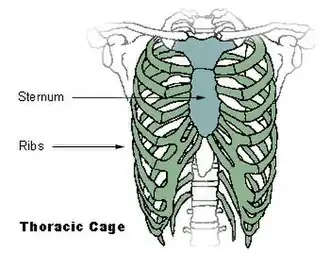

Сверху: грудина окрашена цветом морской волны. Внизу: компьютерная томограмма оскольчатого перелома грудины.[1] Сверху: грудина окрашена цветом морской волны. Внизу: компьютерная томограмма оскольчатого перелома грудины.[1] | |